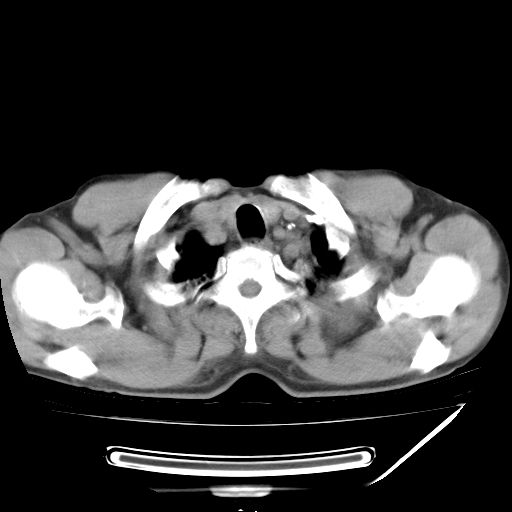

男,59岁,“结核性胸膜炎”30余年,胸部经常疼痛,多次x检查提示“肺部”炎症。腹部疼痛5日,b超提示:“肝内短管结石,余显示不清,建议进一步检查。”

两肺结核并右侧胸腔积液;脾脏、腹腔及腹膜后淋巴结结核[陈旧性];肝内胆管结石

胸部腹部都是结核(双肺。纵隔淋巴结,肝脏,脾脏,肠系膜)

两肺结核并右侧胸腔积液;脾脏、腹腔及腹膜后淋巴结结核[陈旧性];肝内胆管结石。直肠息肉?